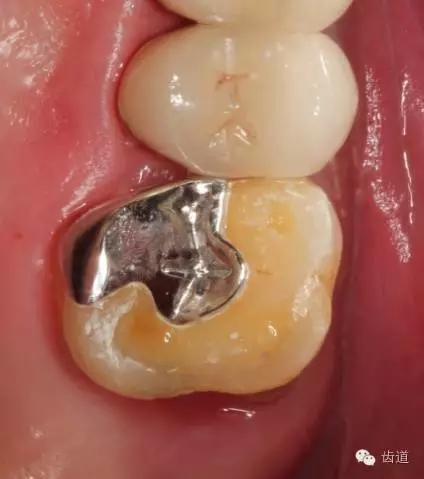

1、磨牙近中崩折舌面行嵌體牙體預(yù)備后

2、金屬鑄造嵌體

3、磨牙金屬鑄造嵌體粘固后